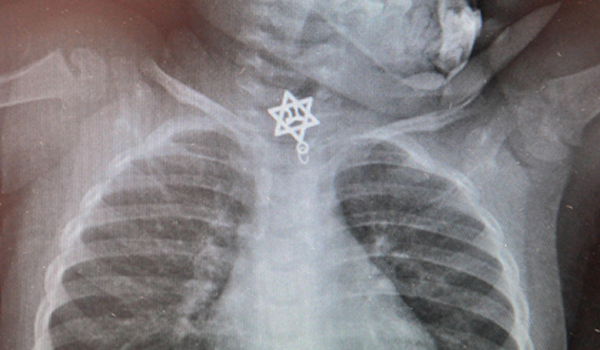

הרופאים בבית החולים קפלן נדהמו לגלות בצילום הרנטגן שביצעו לילדה כי החפץ הזר הוא לא פחות מתליון בצורת מגן דוד עם הכיתוב "חי" בתוכו. רופאה של הפעוטה, ד"ר אודי קצנל סיפר כי "הצורה הגאומטרית עם הלהבים של מגן הדוד שהייתה תקועה לפני הכניסה לוושט בחלק התחתון חייבה שליפה מהירה בחדר הניתוח בהרדמה כללית".

עוד הוסיף ד"ר קצנל: "נערכה תצפית ישירה ללוע ולוושט עם מכשיר אנדוסקופי עדין שאפשר זיהוי וחשיפה בצורה בטוחה של הגוף הזר, והוצאתו בזהירות ובעדינות רבה בסיוע של מלקחיים מיקרו כירורגיים. כעת, לאחר הוצאת מגן הדוד תוכל טליה לחזור לתפקוד רגיל ושגרתי".